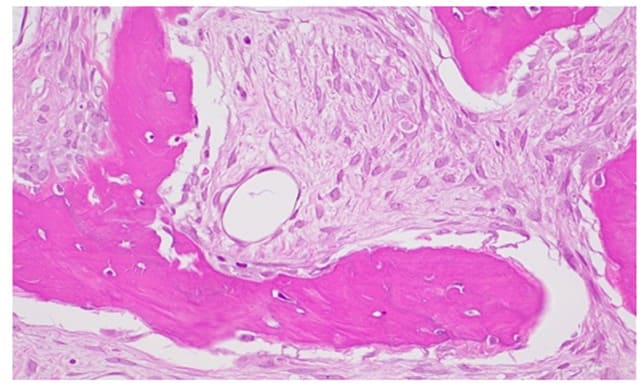

In both cases, histopathological examination revealed osseous tissue characterized by immature bony trabeculae with irregular shapes and sizes, thin and disconnected from each other, surrounded by a fibroblastic stroma, without evidence of osteoblastic activity. At the periphery of the biopsy specimen, the fibro-osseous tissue merged with bone without encapsulation or a demarcation line. This histological pattern is consistent with a diagnosis of fibrous dysplasia. Genetic testing for GNAS gene mutations was not performed because this investigation has a low statistical sensitivity and is useful for uncertain histopathological diagnoses.

Histopathological Features:

Figure 13: H&E 400X 4, fibroblastic stroma with spindle-shaped elements and the absence of osteoblastic rim.